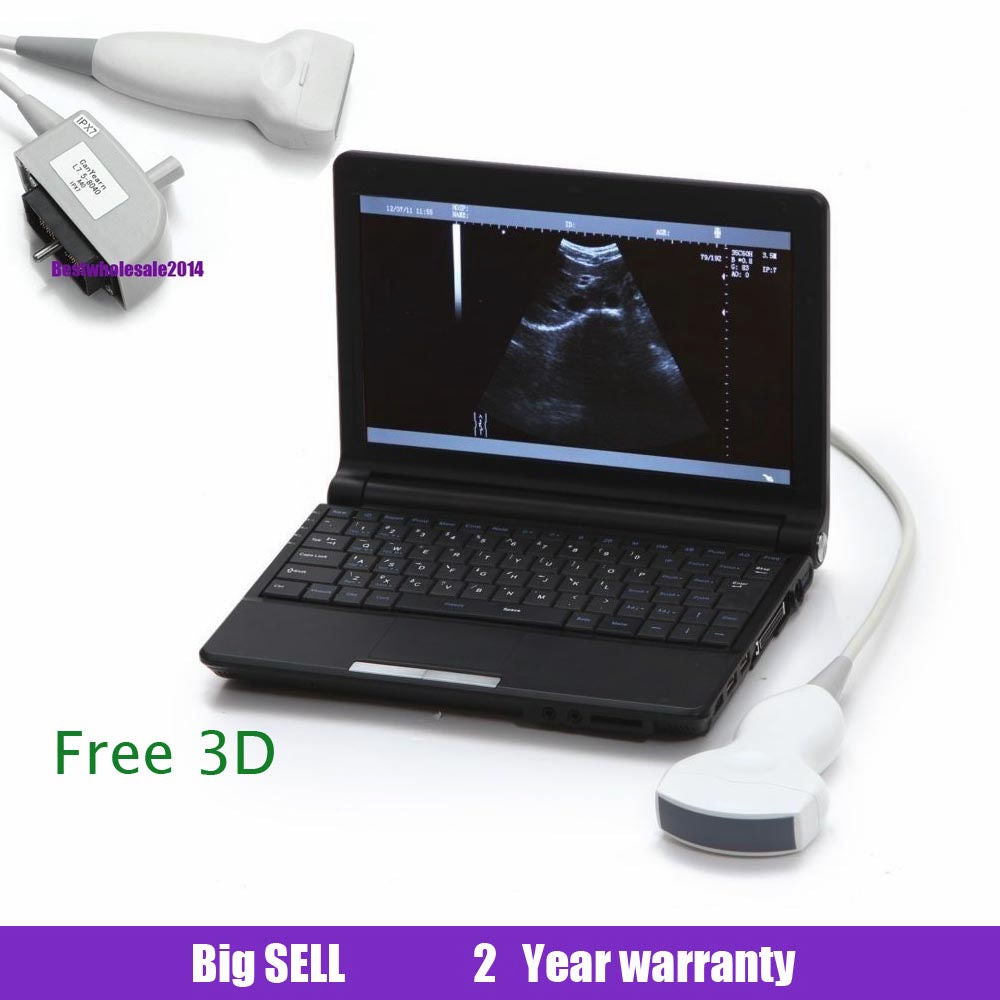

Laptop Ultrasound Machine, Notebook Digital Ultrasound scanner, 3.5 Convex probe